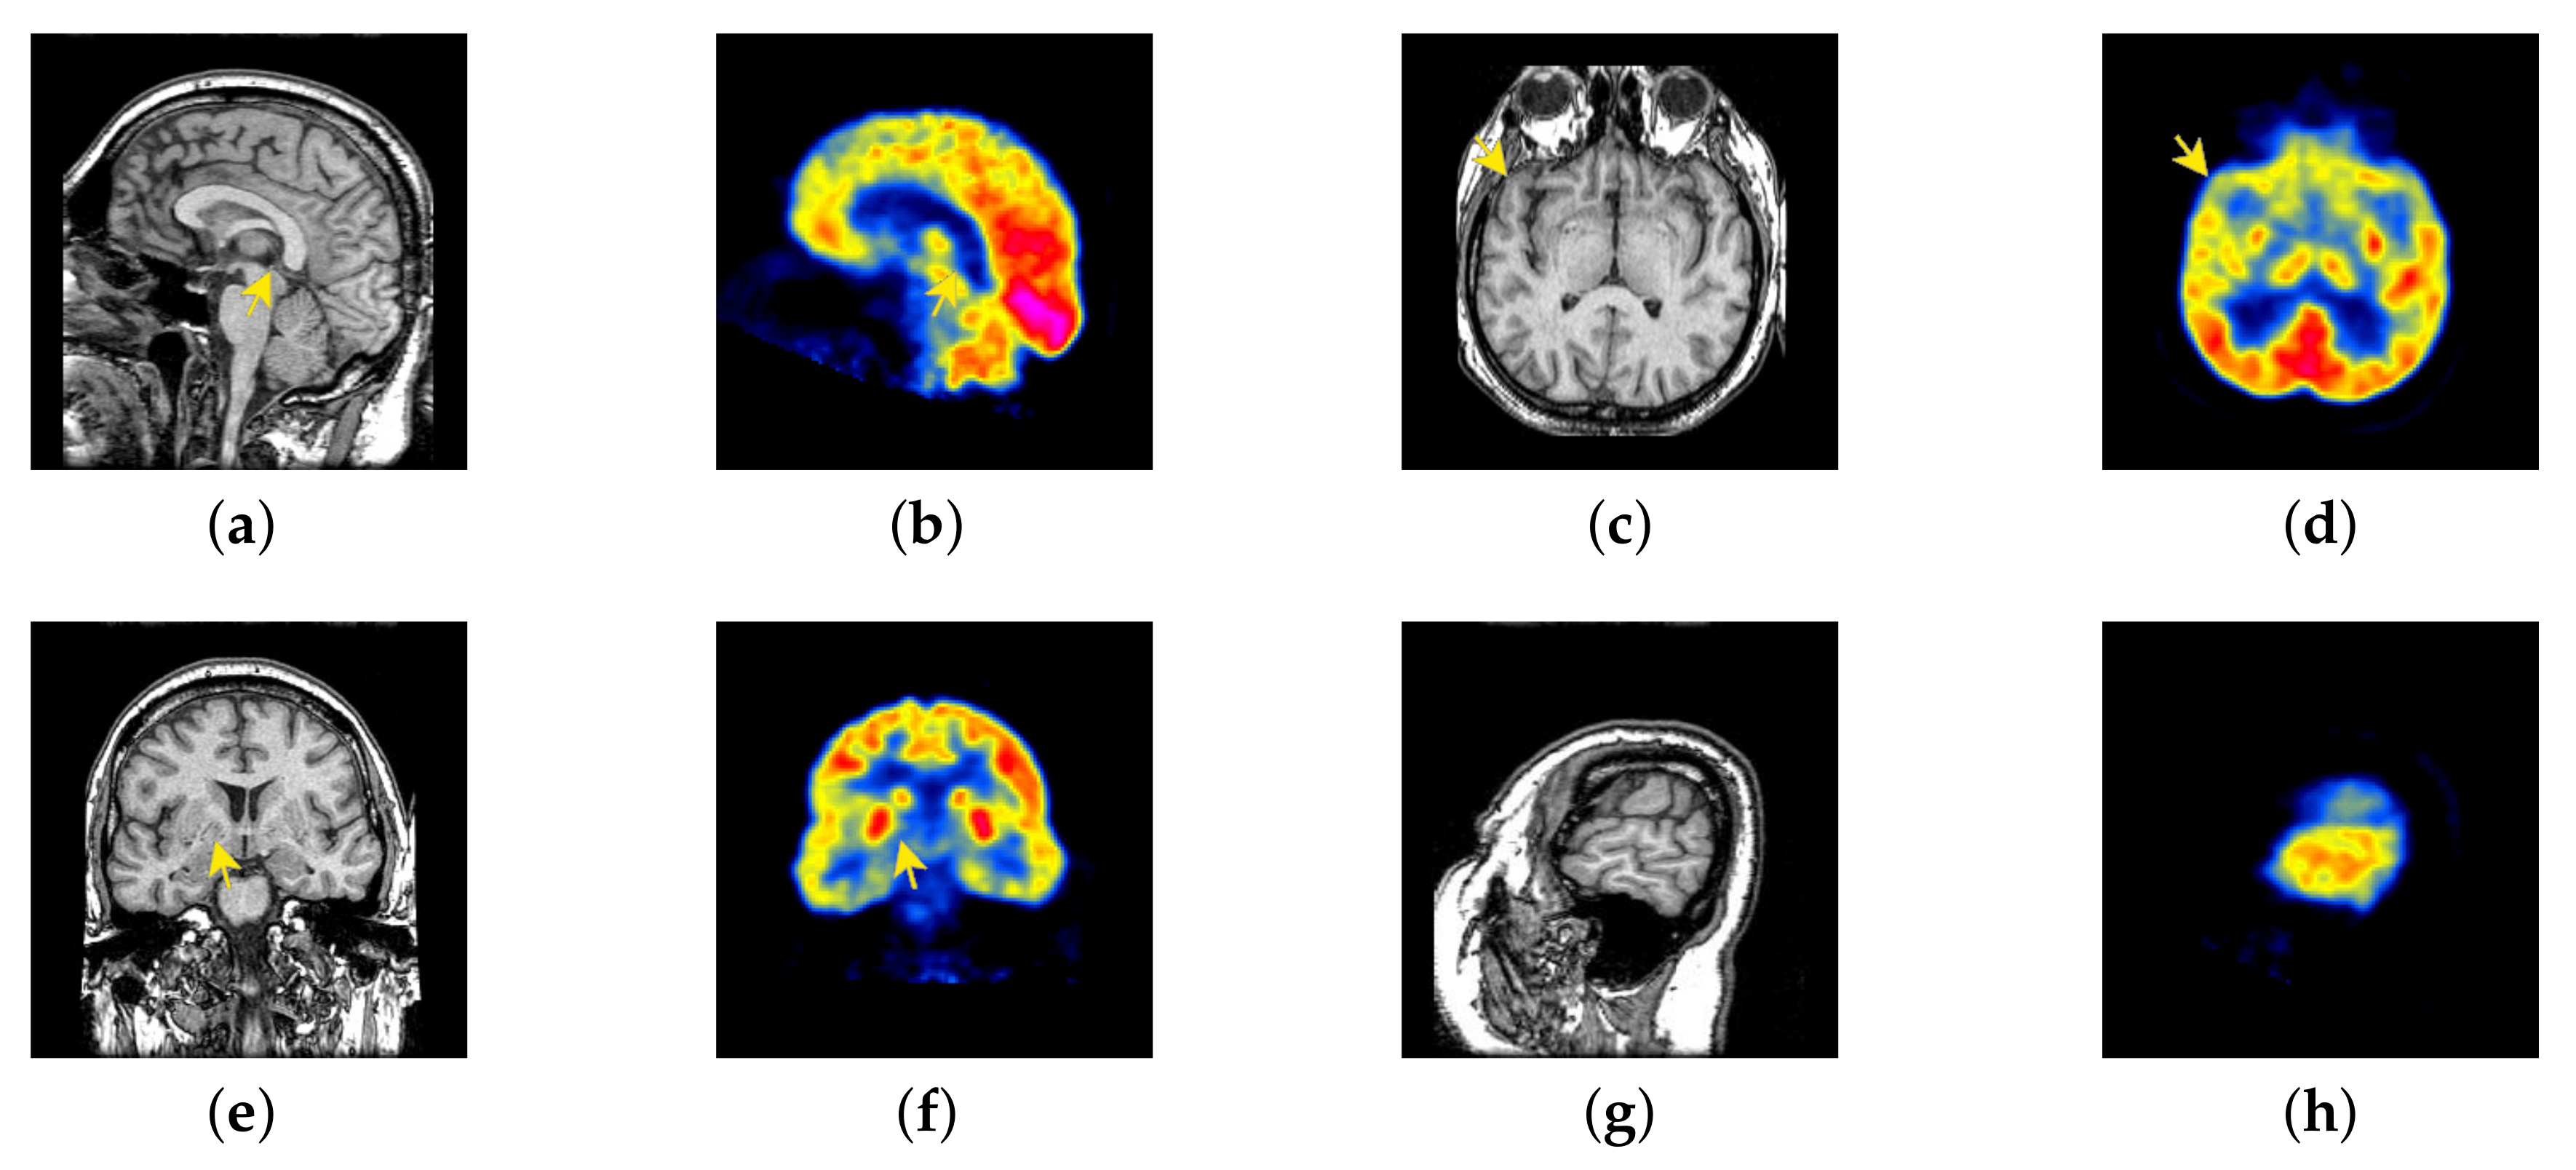

In previous intuitionistic fuzzy sets, scholars usually set to the order of 10 squares. Here, we set to 200, 300, 400, 500, 600, 700, and 800, respectively. Then, the image enhancement experiment is carried out, and the experimental results are shown in Figure 6. According to the results, we can find that, when is set to 500, the result is better than others.

Figure 6.

Source image and its image reconstructed by different algorithms): (a) Source image, (b) = 200, (c) = 300, (d) = 400, (e) = 500, (f) = 600, and (g) = 700, (h) = 800.

4.6. Proposed Framework Analysis

Our proposed FusionNet is inspired by DenseNet. DenseNet has achieved great success in infrared and visible image fusion, however, there are great differences between medical images and two types of images that are mentioned above. DenseNet directly does multi-mode medical image fusion, which is not ideal. Therefore, we have done many improvements. In view of the advantages of intuitionistic fuzzy sets in image processing, we improved the intuitionistic fuzzy sets as part of image preprocessing and added them to our framework. In our experiment, two methods, DenseNet and traditional IFP, were introduced to help us analyze our own methods. Figure 58a,b are source images; Figure 58c is the result of DenseNet fusion; Figure 58d is the fusion result of traditional IFP; Figure 58e is the fusion result of our proposed method.

Figure 58.

Source images and fused medical images obtained by different algorithms: (a) MRI, (b) positron emission tomography (PET), (c) DenseNet, (d) traditional intuitive fuzzy processing (IFP), and (e) FusionNet.

In DenseNet, all middle layer reuses many features of the image, resulting there are few information features, low image brightness, and loss of edge structure information, thus losing the significance of MRI fusion. In traditional IFP, the membership image, the non-membership image and the hesitation image are obtained by the membership function of the multi-mode medical image. Then, the membership image is taken for subsequent fusion operations. This approach allows us to remove more useful information, such as textures of structural images. Considering the disadvantages of DenseNet and traditional IFP, we try to use only the second layer as the unique feature reuse layer to ensure that the respective features of the source image, which can be perfectly reflected in the final fused image. At the same time, the traditional IFP is improved to improve its ability to retain valid information. As can be seen from the experimental results of the following images, FusionNet can retain the structural features and color information required for medical diagnosis in the fused images.